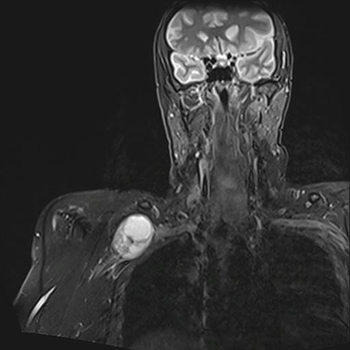

Por ejemplo, puede notarse un bulto en la axila porque tiene una lesión en el nervio axilar; o en la superfice del cuello porque viene del plexo; o un bulto en el antebraazo porque proviene del nervio mediano, etc…

La duración de la cirugía depende un poco de la situación en la que se encuentra el tumor. Si el tumor está situado en un nervio superficial y de fácil abordaje, en menos de 1 hora el tumor puede estar fuera. Si se trata de una tumoración que está dentro del plexo braquial en contacto con grandes vasos o con estructuras dificil de manejar, la duración puede llegar a ser de 6 horas.